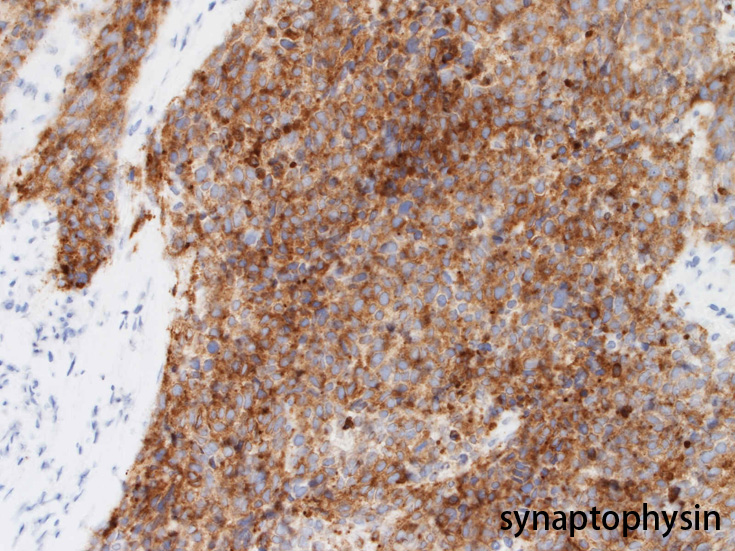

免疫染色 筋マーカ, 神経内分泌マーカほか;本例では神経内分泌マーカがすべて陽性になっている.

Bahrami A, et al., Aberrant expression of epithelial and neuroendocrine markers in alveolar rhabdomyosarcoma: a potentially serious diagnostic pitfall. Mod Pathol. 2008 Jul;21(7):795-806. PMID: 18487991--Free full text

rhabdomyosarcomaではCKなど上皮マーカ-、神経内分泌マーカ-などが発現することがしばしばあり誤診しないことが重要。